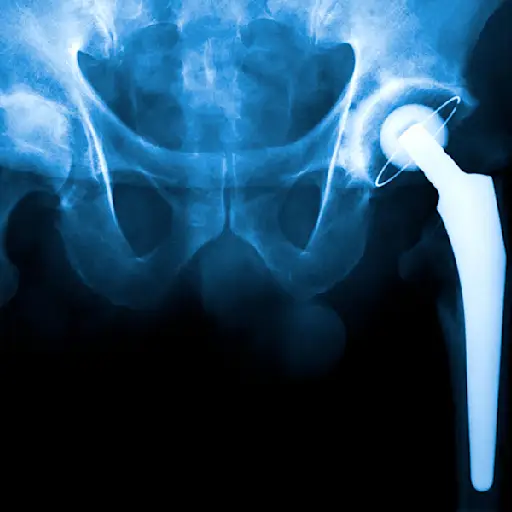

最有可能的是,当时机到来时,你就会知道了。高斯登医生说:“当疼痛或缺乏行动能力每天都在影响你时,如果你因为老年痴呆而取消计划或改变生活,我建议我的病人开始考虑手术。”然而,根据ACR的说法,大多数患有骨关节炎的人不需要关节置换手术。只有在非手术治疗不成功的情况下,才应考虑此选择。(关节置换手术,也称为关节置换术,包括取出磨损的软骨,用金属和塑料制成的关节替换)“最终,你最好自己做决定,”他补充说。

答案是肯定的!尽管所有的手术都有风险,而且做起来都很可怕,但是根据《美国医学杂志》的一项研究,80%到100%的人接受了全膝关节置换术,他们对结果都很满意高速钢杂志。与此同时,一份报告关节成形术注意到全髋关节置换术的满意度约为93%。目前,髋关节或膝关节置换术预计将持续20年或更长时间,使其成为许多人的终身OA解决方案。